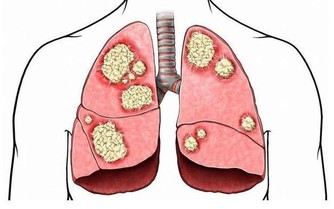

空調清潔不到位或者不及時,散熱片中的細菌超標可達1000倍以上。

這些細菌隨呼吸道進入人體,容易導致人體出現頭暈乏力,甚至患上感冒、鼻炎、哮喘等上呼吸道疾病;重則引起下呼吸道疾病如肺炎,嚴重的還會因為呼吸衰竭而死亡。